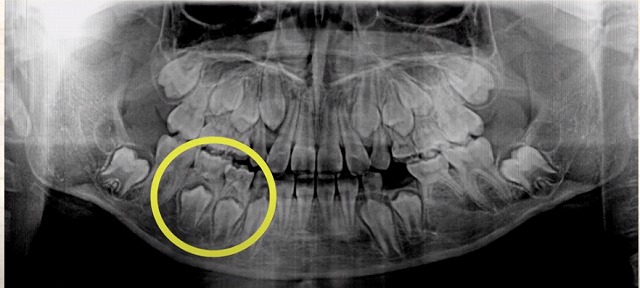

こちらは

子供の歯があって

その下に大人の歯が控えている写真です。

反対側は

子供の歯はありますが

大人の歯が見当たりません

つまり

もともと

大人の歯が

骨の中に控えていない

生えてこない

ということです。